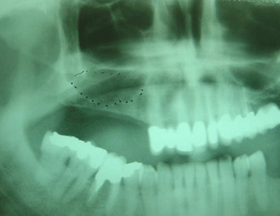

This X-ray shows (dotted area) where BIO-OSS bone grafting material has been surgically placed in order to lift the maxillary sinus floor and in that way increase the height of the jaw bone.

This X-ray shows the build up of bone after 6 months healing period, with sufficient bone height for safe placement of implants.